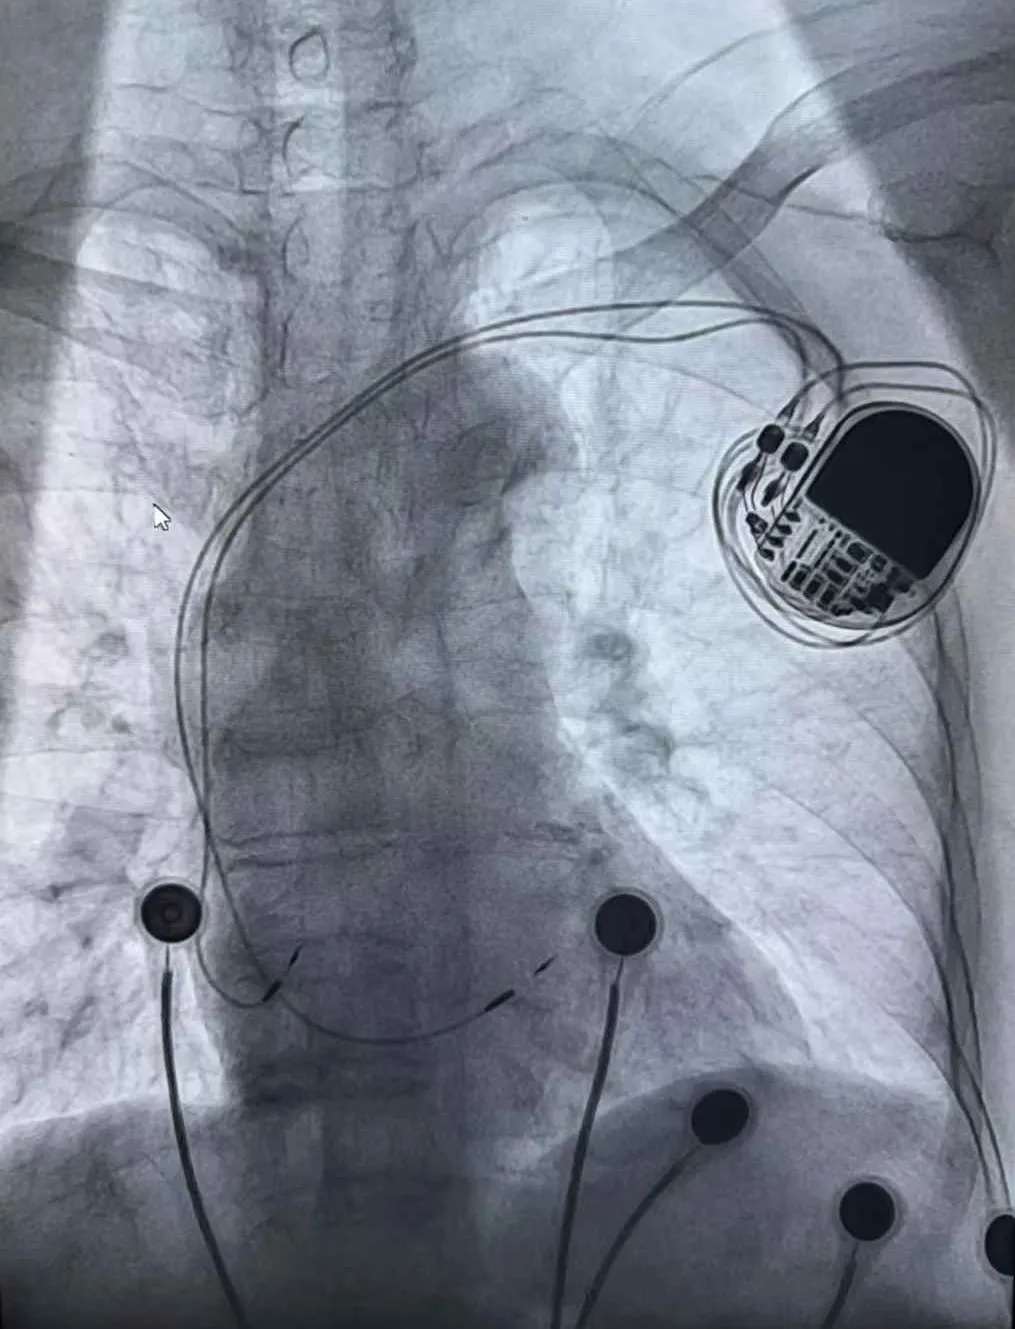

我院成功开展区域首例高难度巴赫曼起搏+左束支区域起搏手术

近日,峨眉山市人民医院心血管介入团队在内二科副主任肖翔的带领下,迎难而上,成功完成一例高难度“巴赫曼起搏+左束支区域起搏”手术。此例手术的成功实施,不仅填补了乐山县级医院该项技术的空白,更标志着我院在心血管疾病精准诊疗领域迈上了新的台阶。

巴赫曼起搏+左束支区域起搏技术代表了为心脏起搏领域前沿突破性技术,其核心优势在于术后产生的QRS心电图波形与健康人无异,能够最大程度地模拟心脏自然的电传导路径,从而显著降低患者发生远期心力衰竭、心房颤动等并发症的风险,为心动过缓患者提供更优质、更符合生理状态的长效治疗效果。

同时,这项技术的难度系数很高,从医生对术者的心脏解剖结构认知、三维空间定位能力、操作精准度及团队默契协作等方面均有极为严苛的要求。